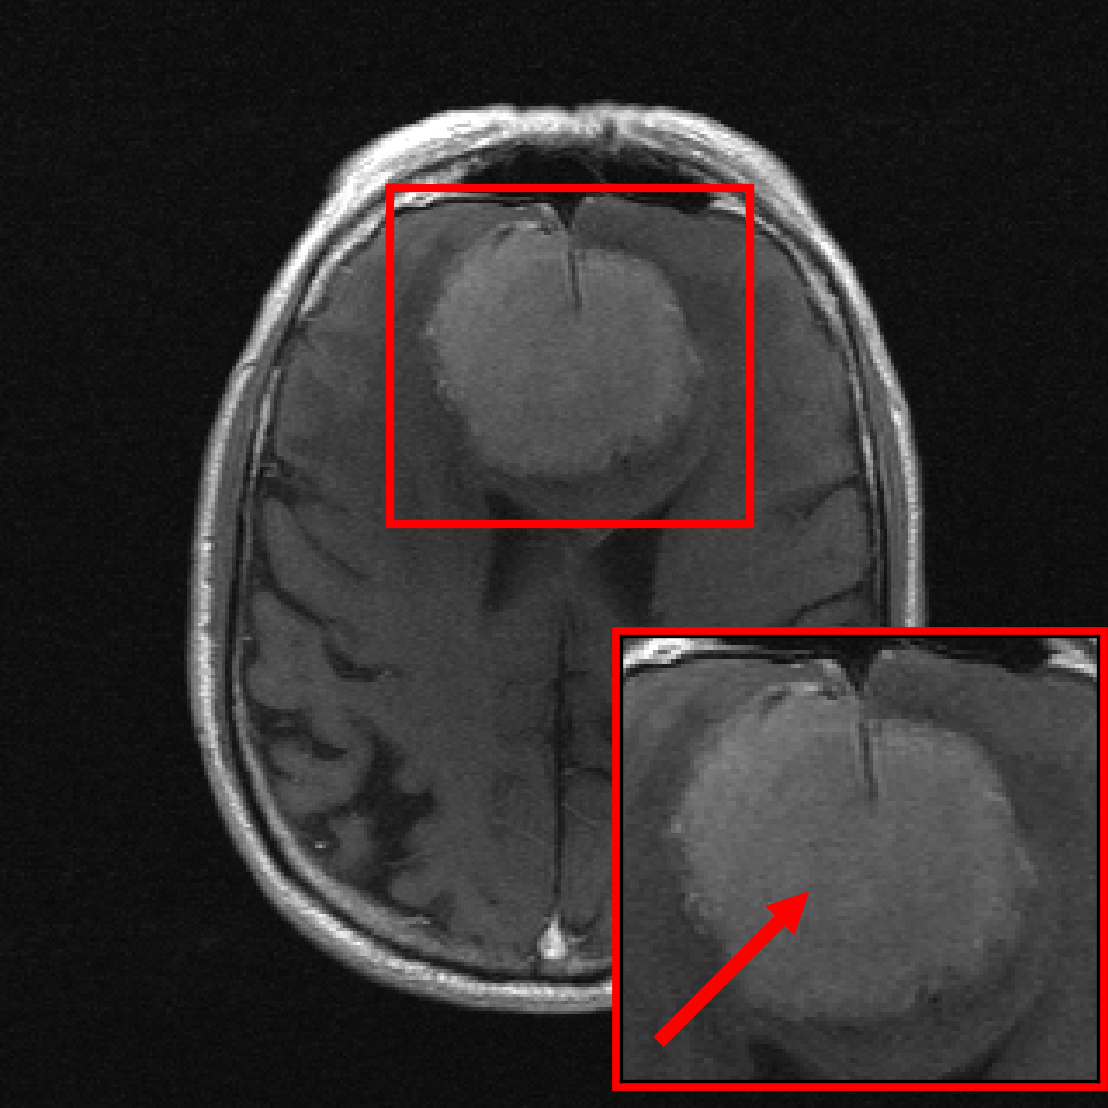

In this section, we investigate the distribution shift from healthy to non-healthy subjects by measuring how well models reconstruct images containing a pathology if no pathologies are contained in the training set. We find that models trained on fastMRI data without pathologies reconstruct fastMRI data with pathologies equally well as the same models trained on fastMRI data with pathologies.

We see that the models trained on show essentially the same performance (SSIM) as models trained on regardless of pathology size. The results indicate that models trained on images without pathologies can reconstruct pathologies as accurately as models trained on images with pathologies. This is further illustrated in Figure 6 (and Figure 16), where we show reconstructions given by the VarNet of images with a pathology: the model recovers the pathology well even though no pathologies are in the training set. Figure 14 in the appendix provides a more nuanced evaluation of the SSIM values for VarNet.